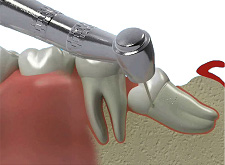

GÖMÜK DİŞ ÇEKİMLERİ

Sürme zamanı geldiği halde, diş dizisinde yer almayarak mukoza altında veya kemik içinde kalmış dişlere gömük dişler denir.

Akıl (20 yaş) dişleri en son süren dişler olduğundan gömüklükleri en sık görülen dişlerdir. 20 yaş dişleri temizleme güçlüğünden dolayı kolay çürümeleri ve sürme zorluğu nedeniyle gömük kalırlar.